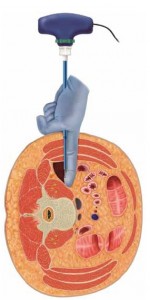

El procedimiento DLIF (Direct Lateral Interbody Fusion) de fusión intersomática lateral directa ofrece a los cirujanos especialistas en columna vertebral una solución completa mínimamente invasiva para el tratamiento de las patologías lumbares degenerativas. Al utilizar un abordaje lateral directo de la columna vertebral, este procedimiento permite colocar un injerto intersomático grande en el espacio intervertebral como apoyo de la columna anterior al tiempo que evita los inconvenientes de los abordajes anterior o posterior tradicionales. El procedimiento DLIF incorpora un conjunto completo de instrumentos e implantes que incluye la neuromonitorización totalmente integrada, instrumentación de acceso simplificada, implantes de diseño anatómico y sistemas de fijación percutánea.

DESCRIPCIÓN El Sistema vertebral CLYDESDALE™ está formado por cajas intersomáticas de PEEK de diversas anchuras y alturas que incluyen marcadores de tantalio. Estos dispositivos se pueden insertar entre dos cuerpos vertebrales lumbares o lumbosacros para reforzarlos y corregirlos durante las intervenciones quirúrgicas de fusión intersomática lumbar. La forma geométrica hueca de los implantes permite rellenarlos de injerto óseo autólogo.

INDICACIONES El Sistema vertebral CLYDESDALE™ está diseñado para su empleo con injerto óseo autólogo a fin de facilitar la fusión intersomática y debe utilizarse con sistemas de fijación complementarios de uso autorizado en la columna lumbar. El Sistema vertebral CLYDESDALE™ está indicado para pacientes con diagnóstico de discopatía degenerativa en uno o dos niveles contiguos desde L2 a S1. Dichos pacientes con discopatía degenerativa pueden presentar también espondilolistesis o retrolistesis con un grado máximo de 1 en los niveles afectados. La discopatía degenerativa se define como una lumbalgia de origen discógeno con degeneración del disco confirmada por la clínica y mediante estudios radiológicos. Está indicado en pacientes con esqueleto maduro que hayan estado al menos seis meses con tratamiento no quirúrgico. Los implantes se pueden realizar a través de un abordaje lateral mínimamente invasivo.